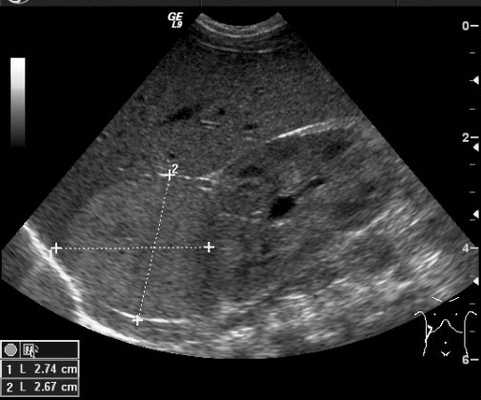

Ультразвуковой метод исследования позволяет выявить наличие опухоли и ее расположение по отношению к внутренним органам. УЗИ позволяет оценить степень местного и отдаленного распространения злокачественного процесса и выявляет метастатическое поражение печени и лимфатических узлов (рис. 4).

Рис. 4. УЗИ образования правого надпочечника